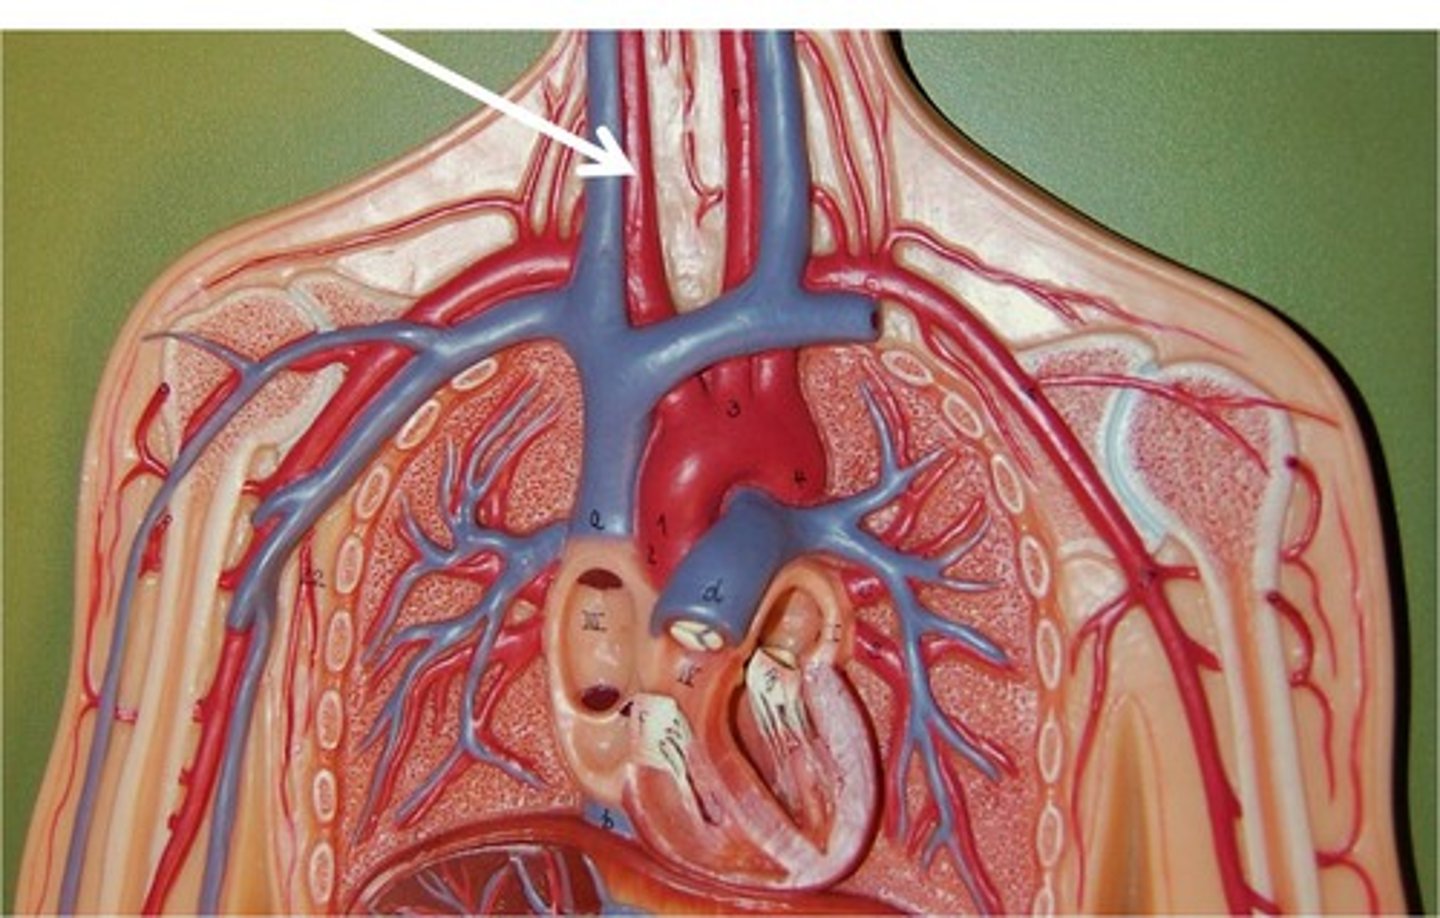

jugular veins

brachiocephalic vein

subclavian vein

superior vena cava

Right common carotid artery

left common carotid artery

right subclavian artery

left subclavian artery